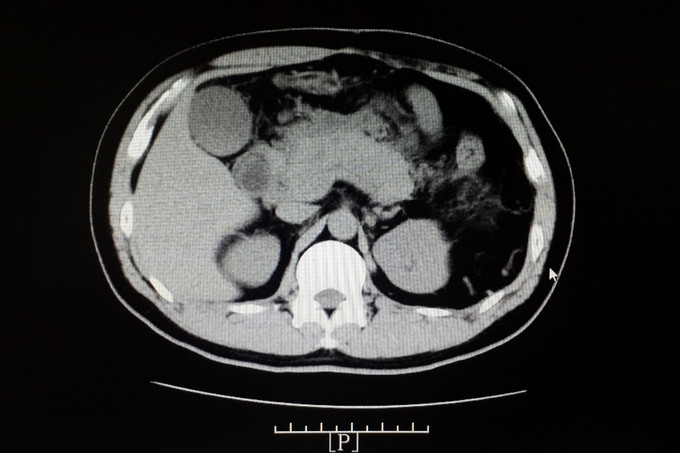

查体:体温:36.8℃(X),血压:130/80mmHg,神清,精神状态可,皮肤及巩膜无黄染,双肺呼吸音清,未及啰音,心率:80次/分,律齐,未及杂音,全腹平软,见陈旧性手术疤痕,全腹压痛,上腹明显,无反跳痛,未及包块,肝脾肋下未及,Murphy征阴性,麦氏点无压痛,肝浊音界存在,肝肾区无叩痛,肠鸣音为4次/分,双下肢不肿。 入院查: 淀粉酶 285.000(U/L)↑,脂肪酶 148.000(U/L)↑; 全血常规五分类:中性粒细胞计数 14.360(10E9/L)↑,白细胞计数 16.520(10E9/L)↑,血红蛋白浓度 176.000(g/L)↑,淋巴细胞比例 0.072↓,红细胞压积 0.502↑,中性粒细胞比例 0.869↑; 感染三项:降钙素原 0.994(ng/ml)↑,白细胞介素-6 52.420(pg/ml)↑,超敏C反应蛋白 212.000(mg/L)↑; 空腹血糖:葡萄糖 8.430(mmol/L)↑; 肾功正常, 肝功能八项:总胆红素 18.100(umol/L),白蛋白 44.000(g/L),直接胆红素 3.200(umol/L),亮氨酰氨基肽酶 34.300(U/L),γ-谷氨酰转肽酶 39.000(U/L),丙氨酸氨基转移酶 21.000(U/L);白、球蛋白比例 1.000↓,球蛋白 46.000(g/L)↑,总蛋白 90.000(g/L)↑,间接胆红素 14.900(umol/l)↑,门冬氨酸氨基转移酶 42.000(U/L)↑; 电解质六项:镁 0.800(mmol/L),钙 2.370(mmol/L),钾 4.170(mmol/L),钠 138.500(mmol/L); 血脂全套(分型+载脂蛋白):总胆固醇/高密度 7.400↑,总胆固醇 8.440(mmol/L)↑,游离脂肪酸 0.830(mmol/L)↑,极低密度脂蛋白 5.680(mmol/L)↑,低密度脂蛋白 1.620(mmol/L)↑,甘油三酯 13.550(mmol/L)↑。 全腹增强CT ,1、考虑:急性坏死性胰腺炎伴胰腺周围局部肠管郁张(炎症具体波及范围如上所述)。 2、考虑:脂肪肝,左肾小结石,脾脏术后缺如。 ((具体描述:胰腺尾部结构不清,胰腺余部体积明显增粗,边缘毛糙、不整,其内密度不匀并可爱可见散在多分小点状钙化影,增强不均匀明显强化,其内可见多发斑片状无强化的坏死区,小网膜囊等胰周、胃周间隙内见大量规则斑片状、片絮、条状密度增高影,增强后轻度强化,两侧肾前筋膜增厚、密度增高,增强后轻度均匀性强化,相邻小肠管轻度扩张,管壁轻度增厚强化,管腔内可见多发气液平征象。)

诊断:1.急性坏死性胰腺炎,2.高脂血症, 入院后予以禁食、抑酸、抗感染、改善胰腺微循环、降血脂、护肝等对症治疗,1周后患者腹痛逐步缓解,肛门恢复排气排便,复查淀粉酶等血生化均正常,复查腹部CT示:胰腺边缘较前清晰。左侧肾上腺略肥大,边缘模糊,考虑炎症累及所致可能性大,现强化较前减轻,余大致同前。2、脂肪肝,左肾小结石,脾脏术后缺如。大致同前。